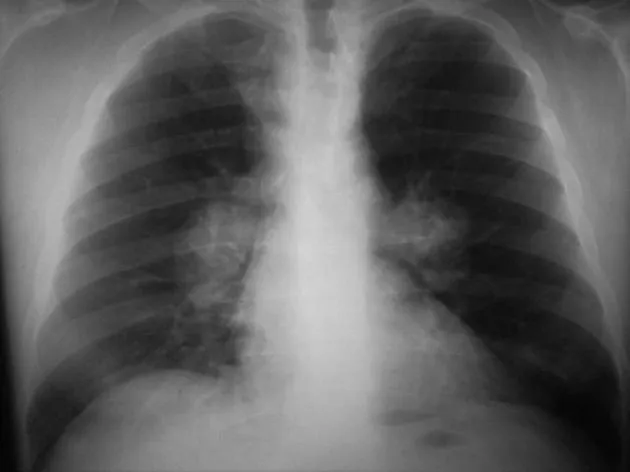

| Pulmonary | >90% | Pneumonia, cavitation, nodules | Chest imaging, sputum | Good prognosis if localized |